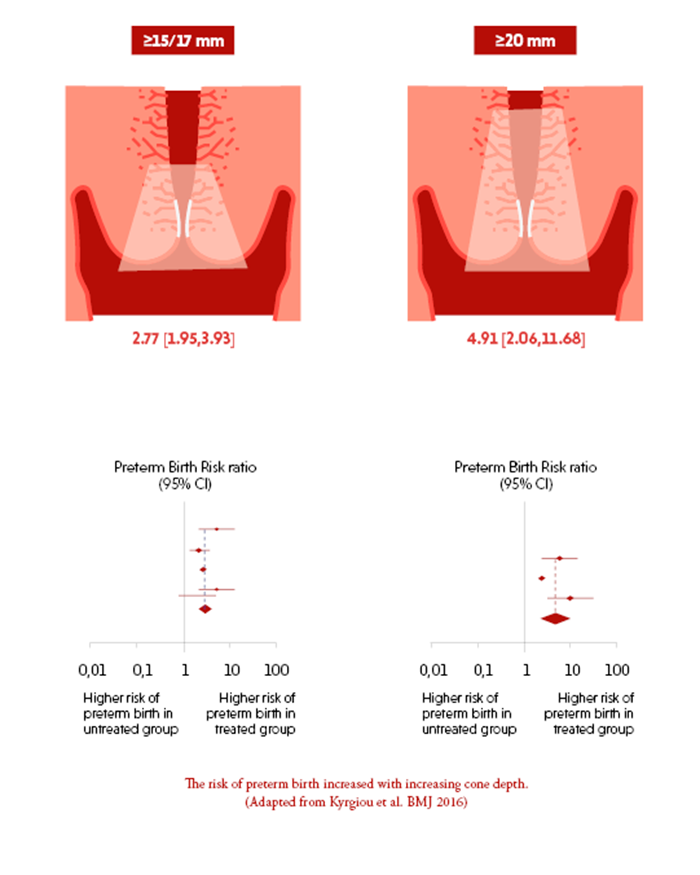

Pregnancy and Birth (Asian) | BSI Catalog, Reproductive impact of local CIN treatment,

Reproductive impact of local CIN treatment, ectopic-pregnancy-unit-kk-,